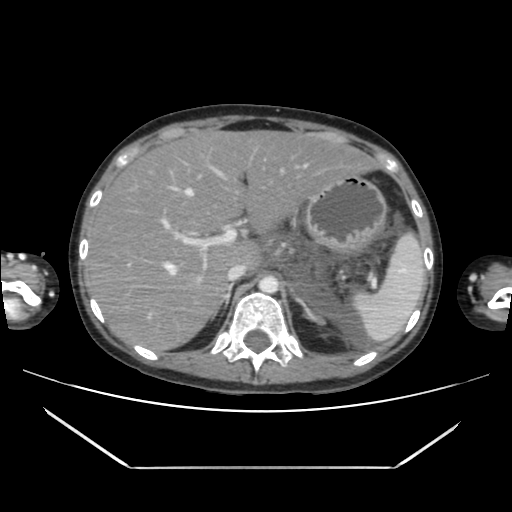

환자의 복부 CT 영상을 환자의 머리쪽에서부터 다리 쪽 방향으로 중간중간 한 컷씩 나열해 보았다.

CT 영상만 보더라도 환자는 괴사성췌장염으로 일부췌장과 주변 조직들이 녹아 있음을 알 수 있고, 이로 인해 복막염, 이차적으로 장마비 소견까지 보이고 있었다.